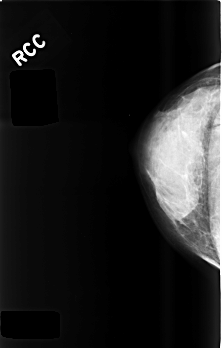

C_0477_1.RIGHT_MLO

C_0477_1.RIGHT_CC

RIGHT_CC LINES 4520 PIXELS_PER_LINE 2880 BITS_PER_PIXEL 12 RESOLUTION 50 NON_OVERLAY

RIGHT_MLO LINES 4480 PIXELS_PER_LINE 2912 BITS_PER_PIXEL 12 RESOLUTION 50 NON_OVERLAY